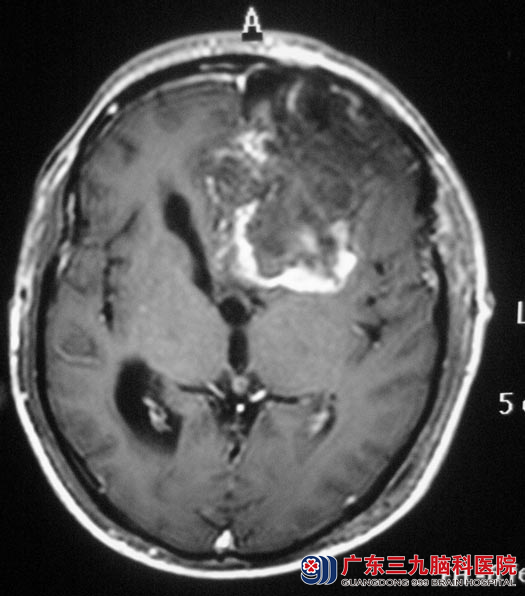

当地医院CT结果提示:左侧额叶占位性病变,考虑胶质瘤的可能。

入住广东三九脑科医院综合神经外科,完善相关检查后,鲁明主任主刀,在全麻下行左侧额叶肿瘤切除+去骨瓣减压术,术中见肿瘤呈胶冻样,质地硬,血供丰富,左侧大脑前动脉被肿瘤包裹,显微镜下予肿瘤分块切除,术后病理证实为:左侧额叶胶质母细胞瘤(WHO IV级)。之后梁老师还需要进一步的放化疗。